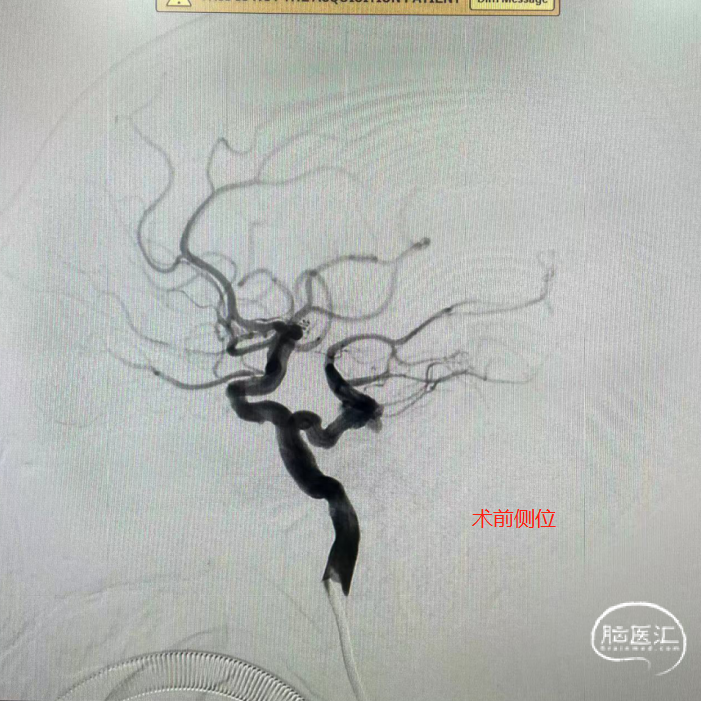

【病例夹】王飞教授:原始三叉动脉瘤栓塞

病例介绍